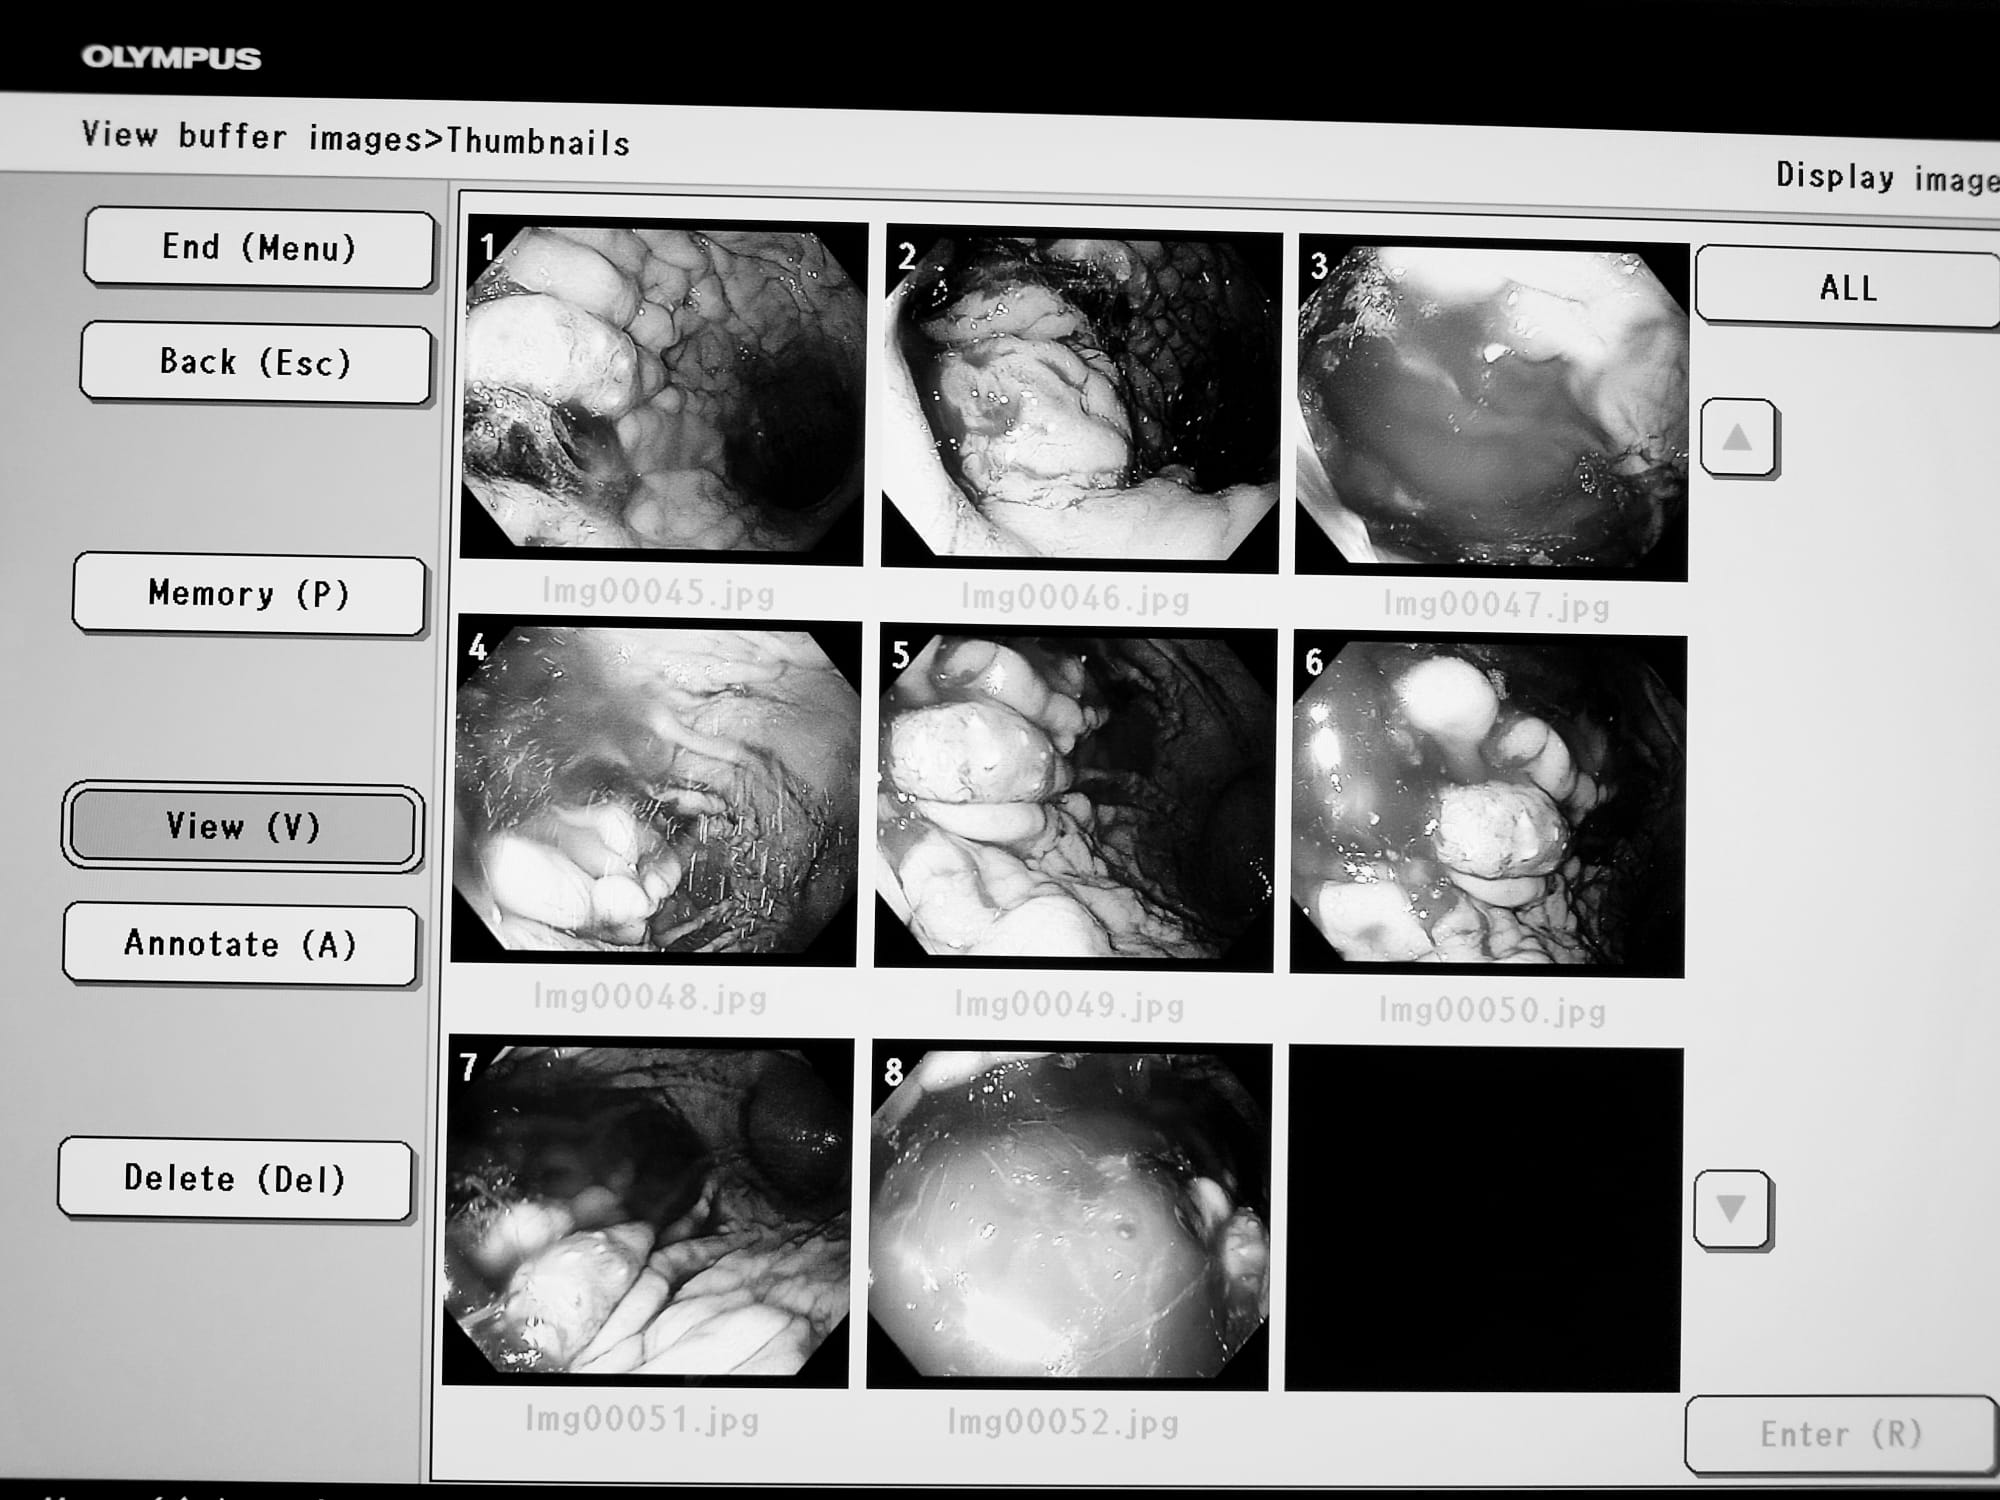

„O afecțiune depistată la timp este mai ușor de tratat, iar prognosticul pentru pacient este mult mai bun. Este un aparat ultraperformant, mai ales datorită tehnicii NBI-narrow band imaging. Această tehnică ajută în depistarea precoce a tumorilor digestive și a altor leziuni inflamatorii din peretele digestiv. Acest fel de aparat există în clinicile și spitalele universitare din țară”, a menționat dr. Roxana Gheorghițoiu, medic specialist gastroenterologie din cadrul Spitalului Județean de Urgență Târgu-Jiu.